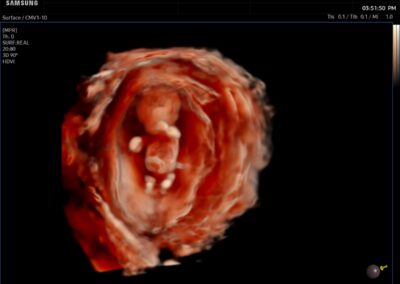

Comprehensive, advanced and expert MFM care for high-risk pregnancies

- Intrauterine growth restriction